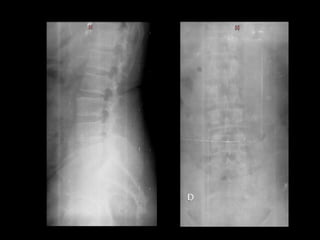

Leitora carregou 2 IPs no mesmo Cassete

Erro no Apagamento